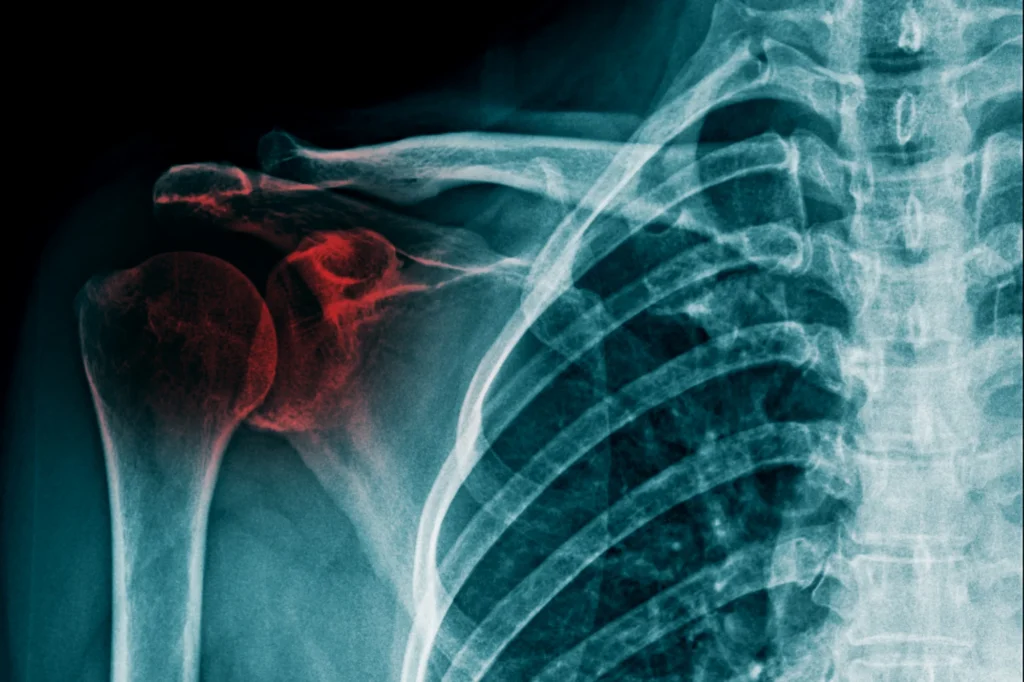

Shoulder Fractures

Fractures are a frequent result of fall-related shoulder trauma. The three bones most commonly involved are the proximal humerus (the top portion of the upper arm bone), the clavicle (collarbone), and the scapula (shoulder blade).

Proximal humerus fractures tend to be especially common among older adults who fall onto an outstretched arm. Symptoms may include deep pain, swelling, and bruising. Clavicle fractures may produce a visible bump along the collarbone and sharp pain with arm movement. Scapular fractures are less common and typically result from higher-energy impacts.

Shoulder fracture

Not all fractures require surgery. Many heal well with a period of immobilization in a sling followed by guided rehabilitation. However, fractures that are significantly displaced, involve the joint surface, or break the bone into multiple fragments may require surgical repair to restore proper alignment.